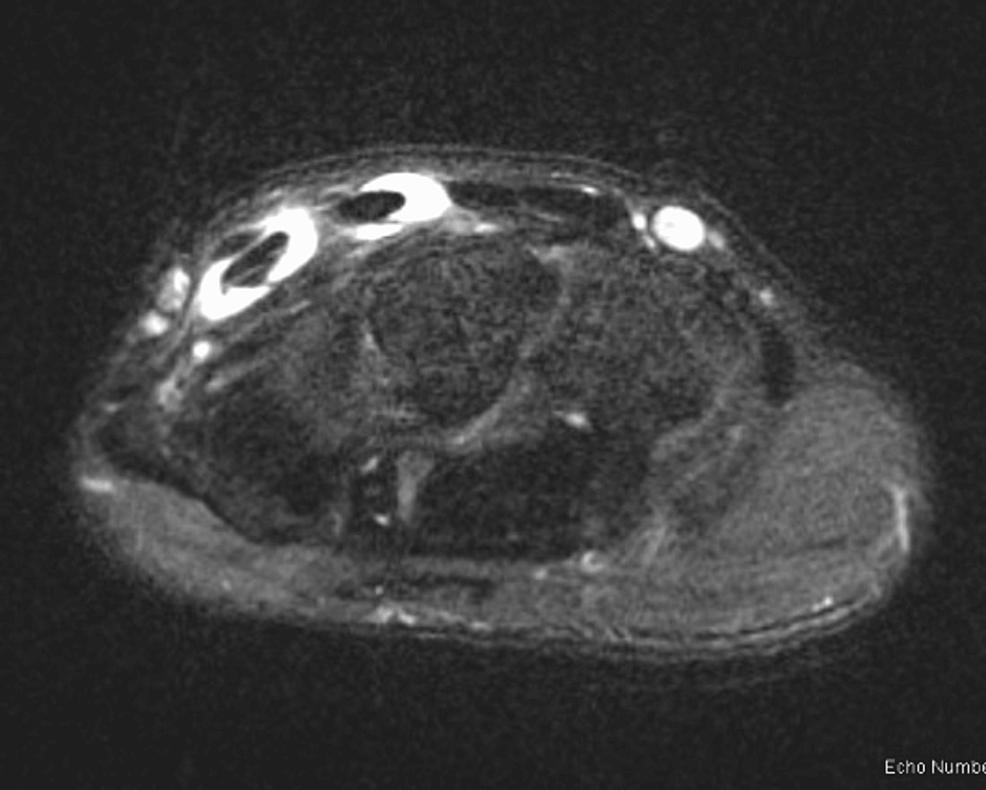

From www.researchgate.net

AB Transverse axis sonogram of the first dorsal compartment show (A) a Dorsal Compartment Release Recovery dequervain’s release post operative rehabilitation protocol following surgery: Start by walking a little more than you did the day before. this complication is best avoided by carefully limiting the release to the thickest middle 2 cm of the first dorsal. learn how to care for yourself at home after surgery to release a tendon that runs along. Dorsal Compartment Release Recovery.